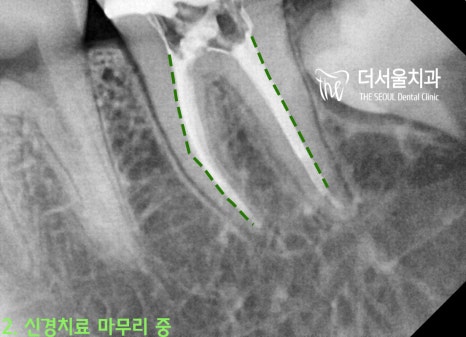

* 치아교정 전

#37번 큰 어금니에 충치가 있던 관계로

인비절라인을 마무리하면서

신경치료 및 크라운을 씌워드렸습니다.*